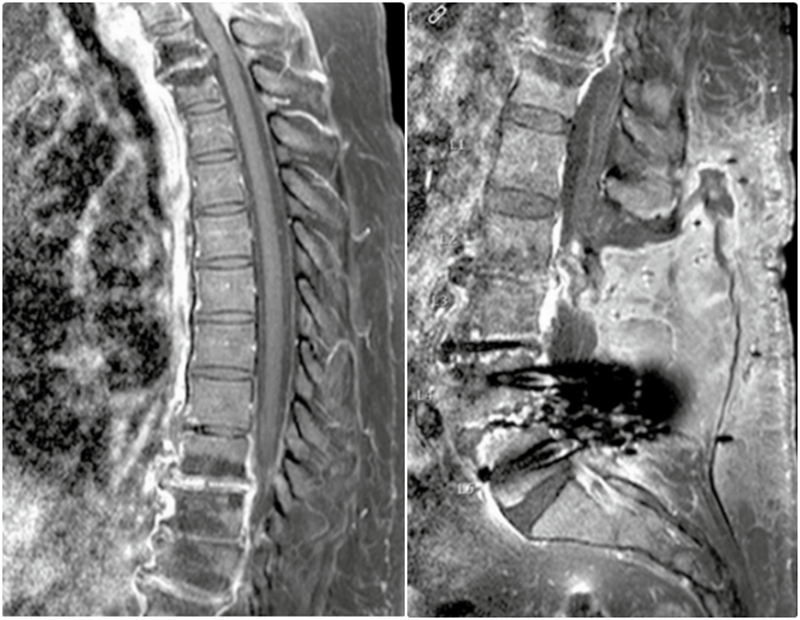

胸椎(A)和腰椎(B)脊柱MR图像显示C7-T1以及T1-2和T9-12椎间盘内有一些强化。从T9到T12也有腹侧硬膜外强化

腰椎MRI,L2和L3椎体强化,骨髓水肿,伴椎前/椎旁软组织肿胀,弥漫性椎间盘膨出,黄韧带增厚,椎管狭窄

腰椎MRI,L2/3明显狭窄,左侧明显,伴椎间盘炎和中度硬膜囊压迫,周围可见软组织水肿,左侧腰大肌轻度水肿。